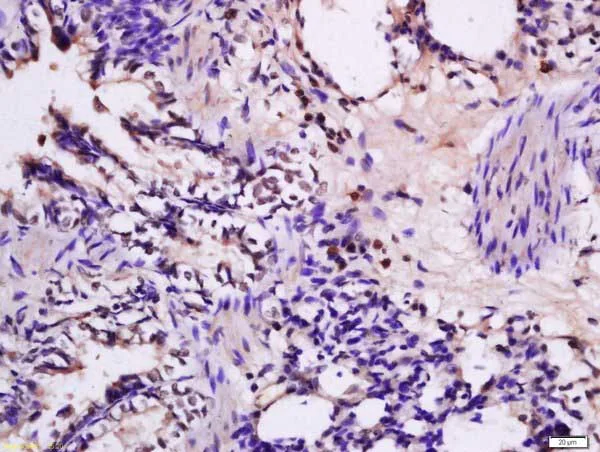

Immunohistochemistry (Formalin/PFA-fixed paraffin-embedded sections) - Anti-FKLF / KLF11 antibody (AB217311)

Immunohistochemical analysis of formalin-fixed, paraffin-embedded rat lung tissue labeling FKLF / KLF11 with ab217311 at 1/200 dilution, followed by conjugation to the secondary antibody and DAB staining.